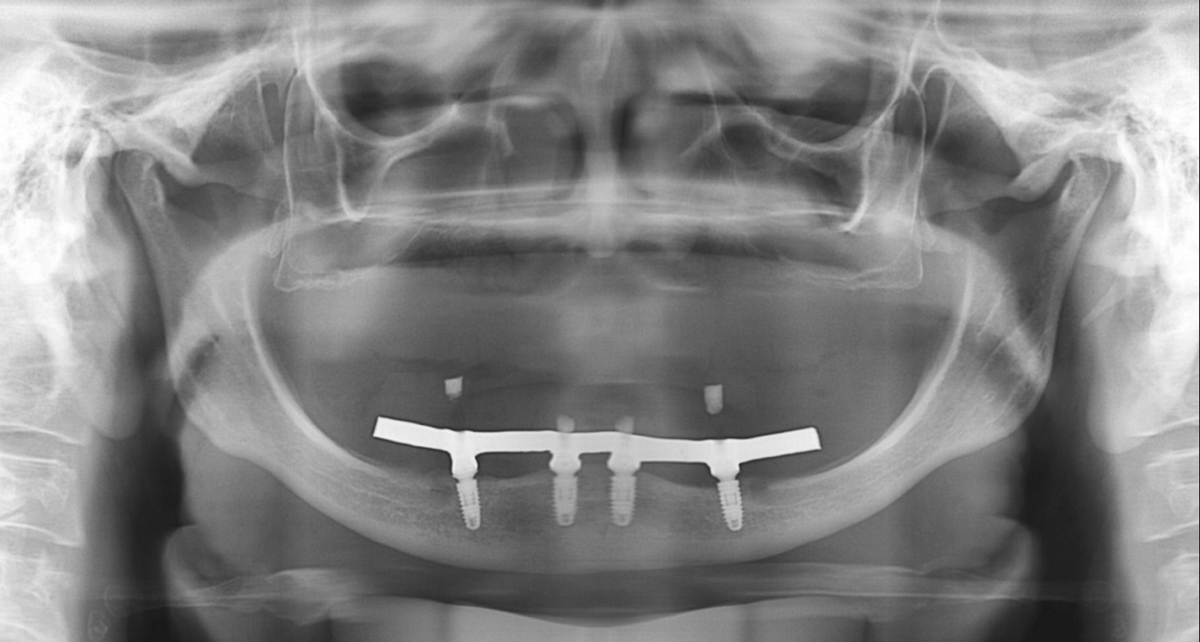

PRÓTESE TOTAL FIXA EM IMPLANTES

E.M.S.